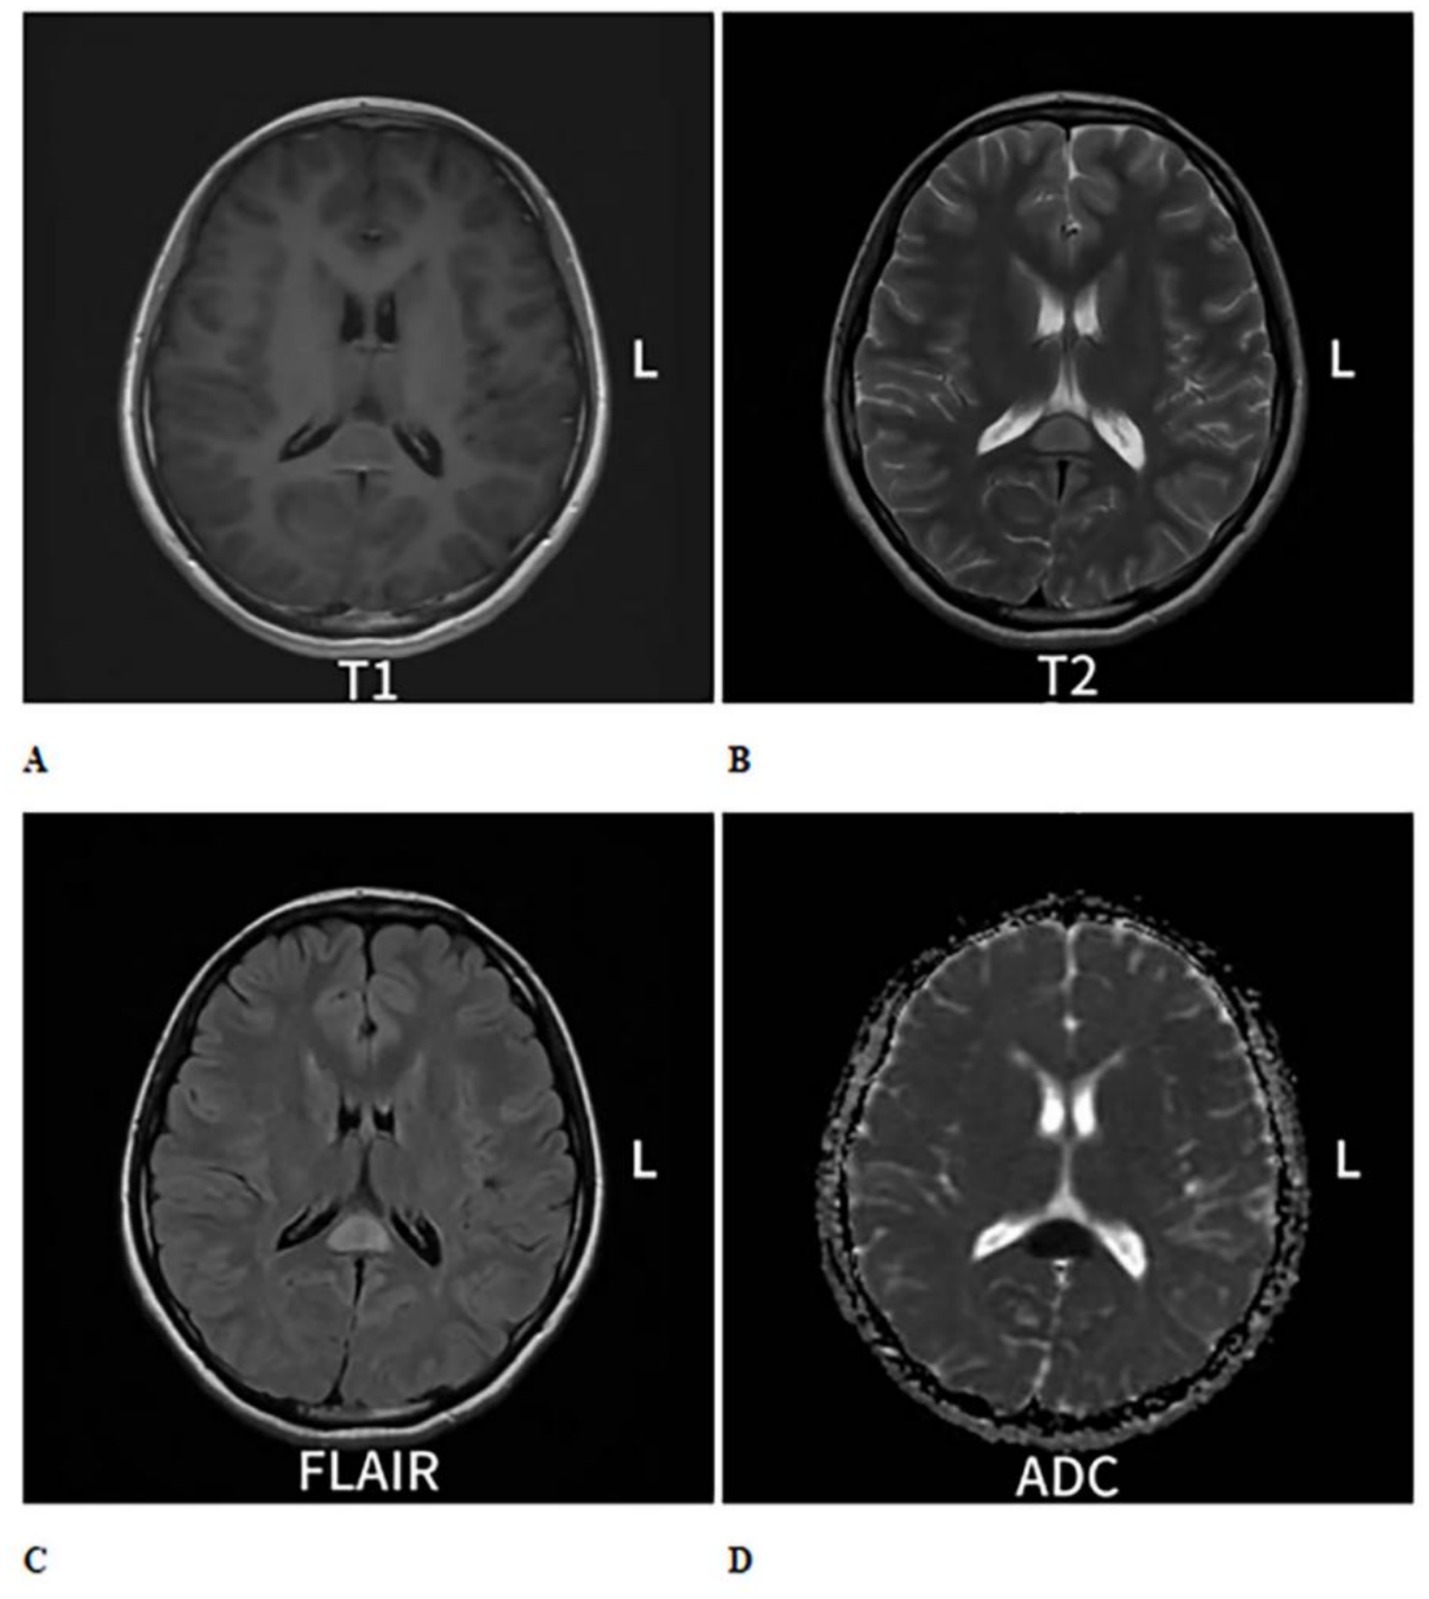

Figure 1

Cranial MRI plain scan with enhancement shows an oval-shaped abnormal signal in the midline area of the splenium of the corpus callosum. (A) On T1-weighted imaging (T1WI), it exhibits isointense to slightly hypointense signals (B), while on T2-weighted imaging (T2WI), it shows hyperintense signals. (C) On T2 fluid-attenuated inversion recovery (T2-FLAIR), the signal is also hyperintense. (D) Diffusion-weighted imaging (DWI) indicates restricted diffusion within the lesion, and no significant change is observed on enhanced scans.